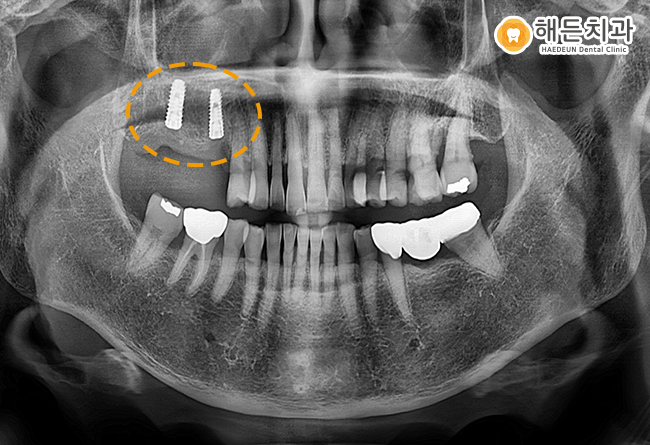

임플란트 식립 후 사진입니다.

현재 치아 뿌리 역할을 하는 인공치근인 픽스처만 식립되어 있는 상태이며, 커버스크류를 체결해놓은 상태인데요.

쉽게 말하면, 픽스처 윗 부분을 막아주는 뚜껑이라고 생각하시면 이해가 쉬운데

픽스처에 이물질이 들어오지 못하게 막아주는 역할을 한답니다.

임플란트는 잇몸뼈에 인공치근을 식립한 뒤,

뼈와 단단하게 붙을 수 있는 충분한 기간을 기다려 준 후 최종보철물(크라운)을 올려주게 됩니다.

픽스처가 잇몸뼈에 충분히 유착할 수 있도록 기다린 후, 최종 치료 마무리까지 신경 써 도와드리기로 했습니다. 😊